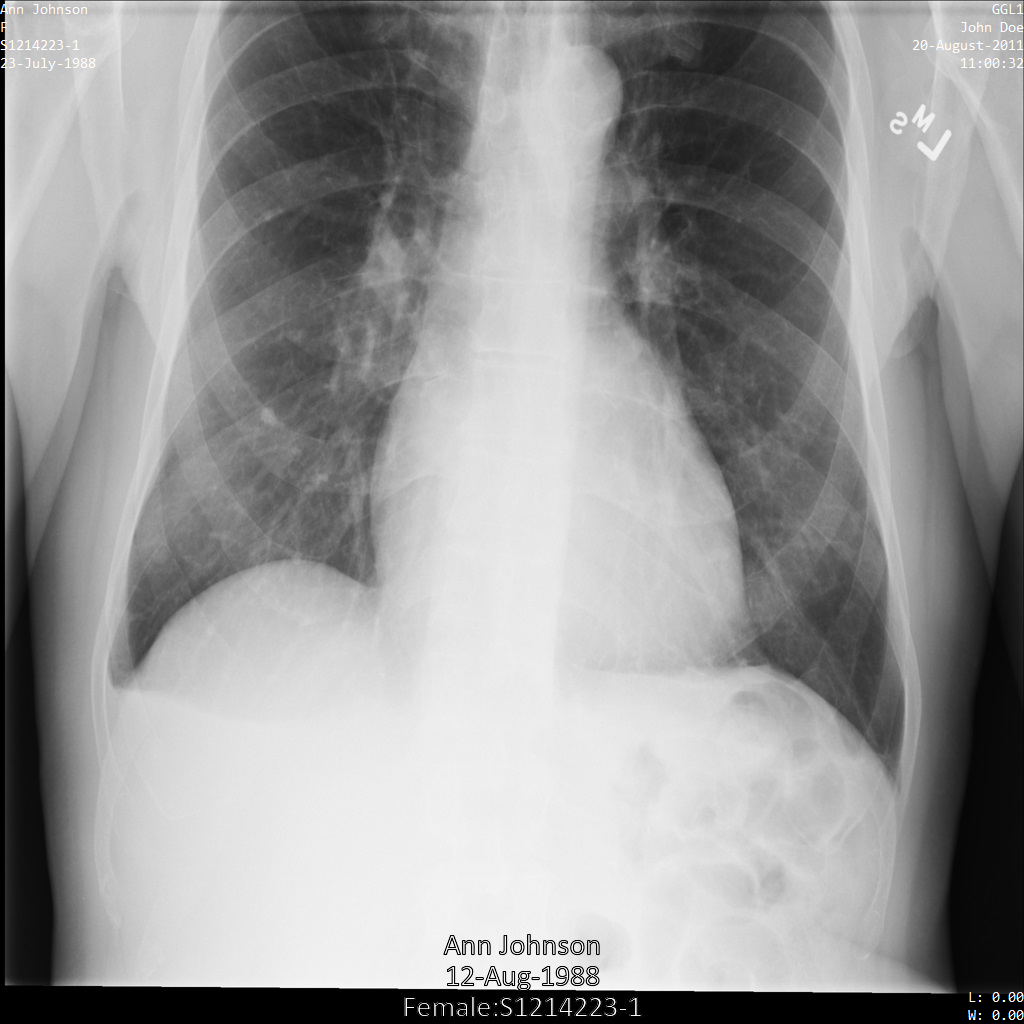

Después de enviar la imagen a la API de Cloud Healthcare, la imagen aparece de la siguiente manera. De las etiquetas proporcionadas en la removelist, solo se quita PatientBirthDate en la imagen, ya que es la única etiqueta de la lista de eliminación que corresponde a los metadatos visibles en la imagen.

Si bien PatientBirthDate en la esquina superior de la imagen se ocultó de acuerdo con la configuración de la removelist, la PHI de efecto quemado que se encuentra en la parte inferior de la imagen permanece. Para quitar también el texto quemado, consulta Cómo ocultar el texto quemado de las imágenes.